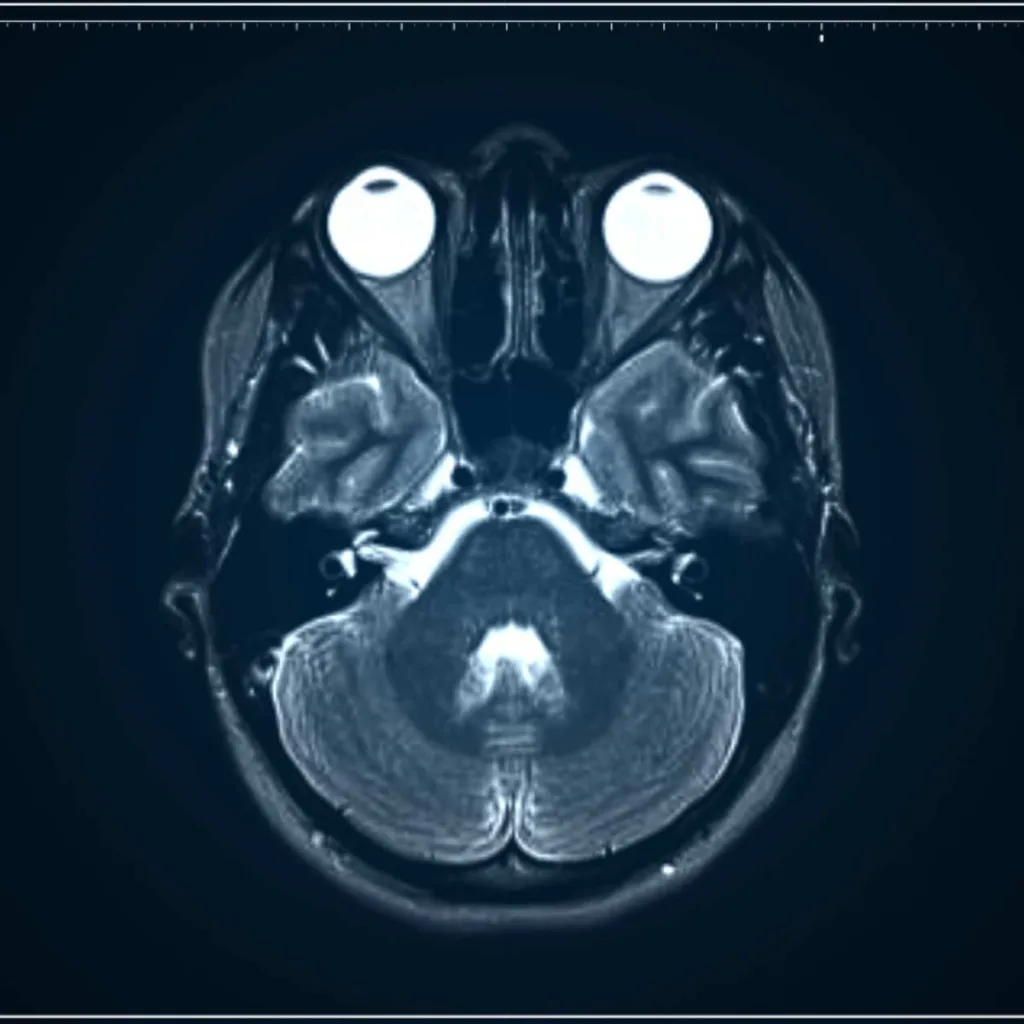

Resonancia Magnética de Cabeza